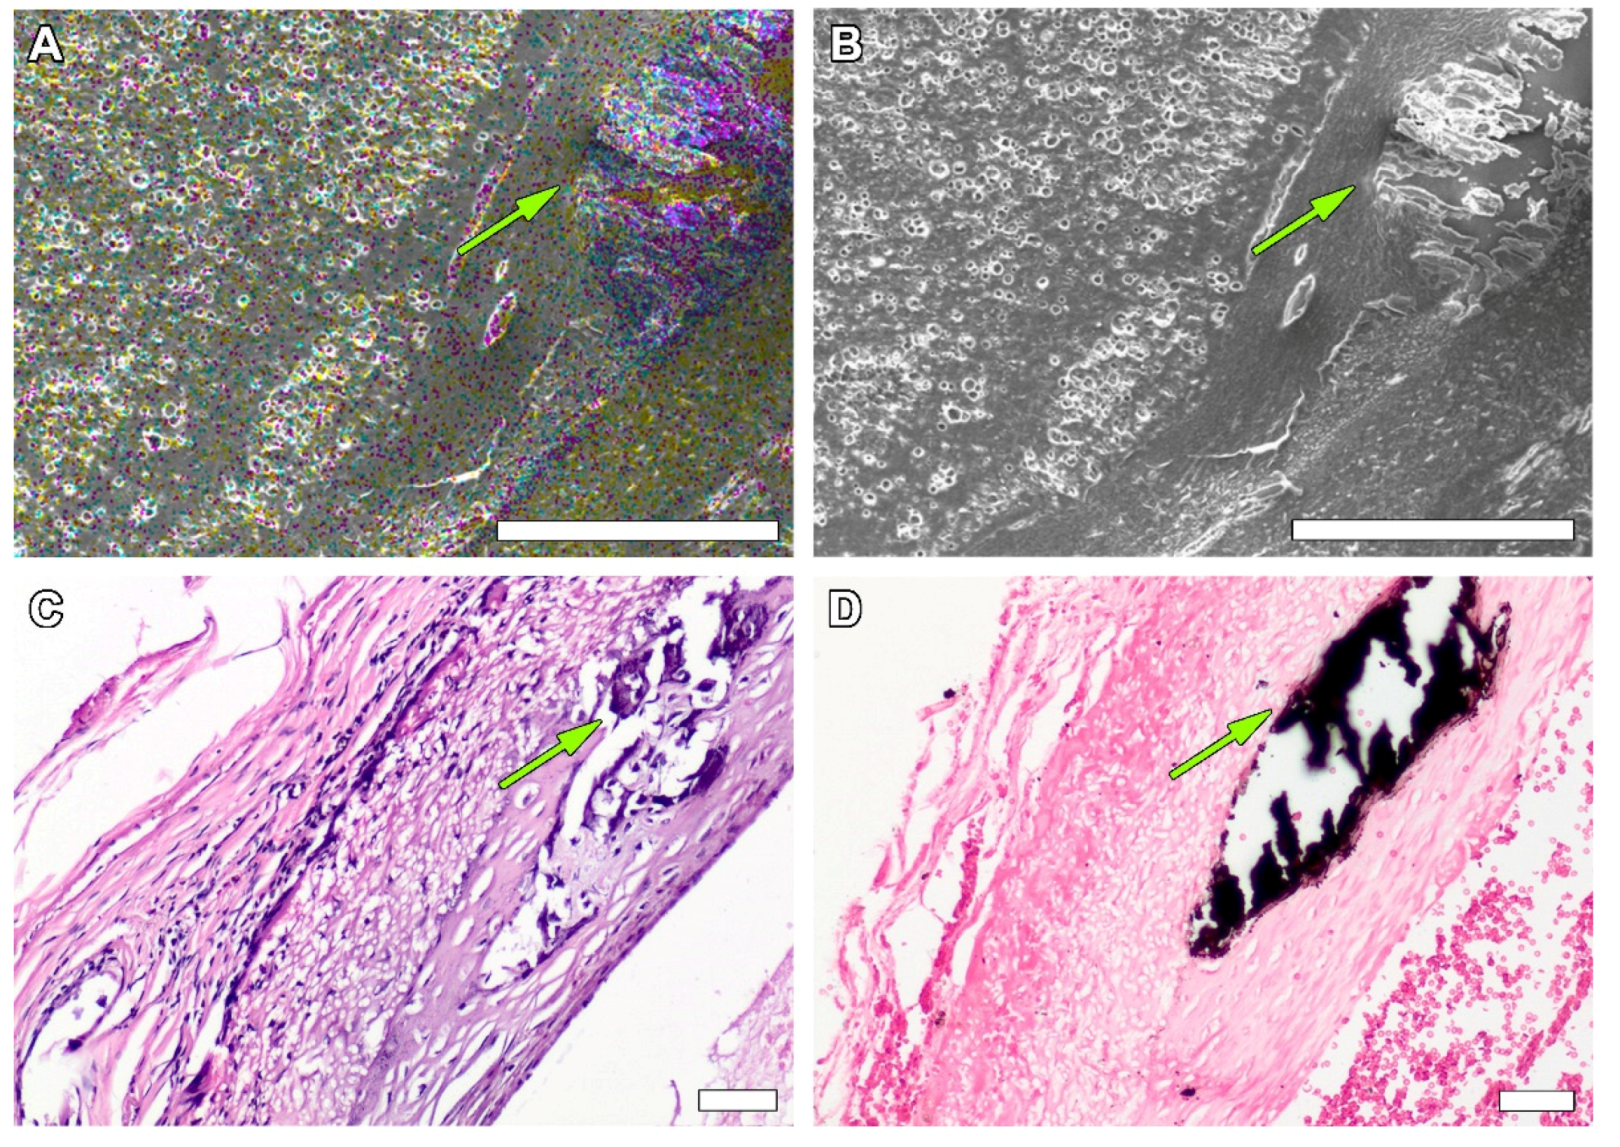

3.1. Non-Implanted Scaffolds

3.3. PCL Graft Transformation in Dynamics

4. Discussion